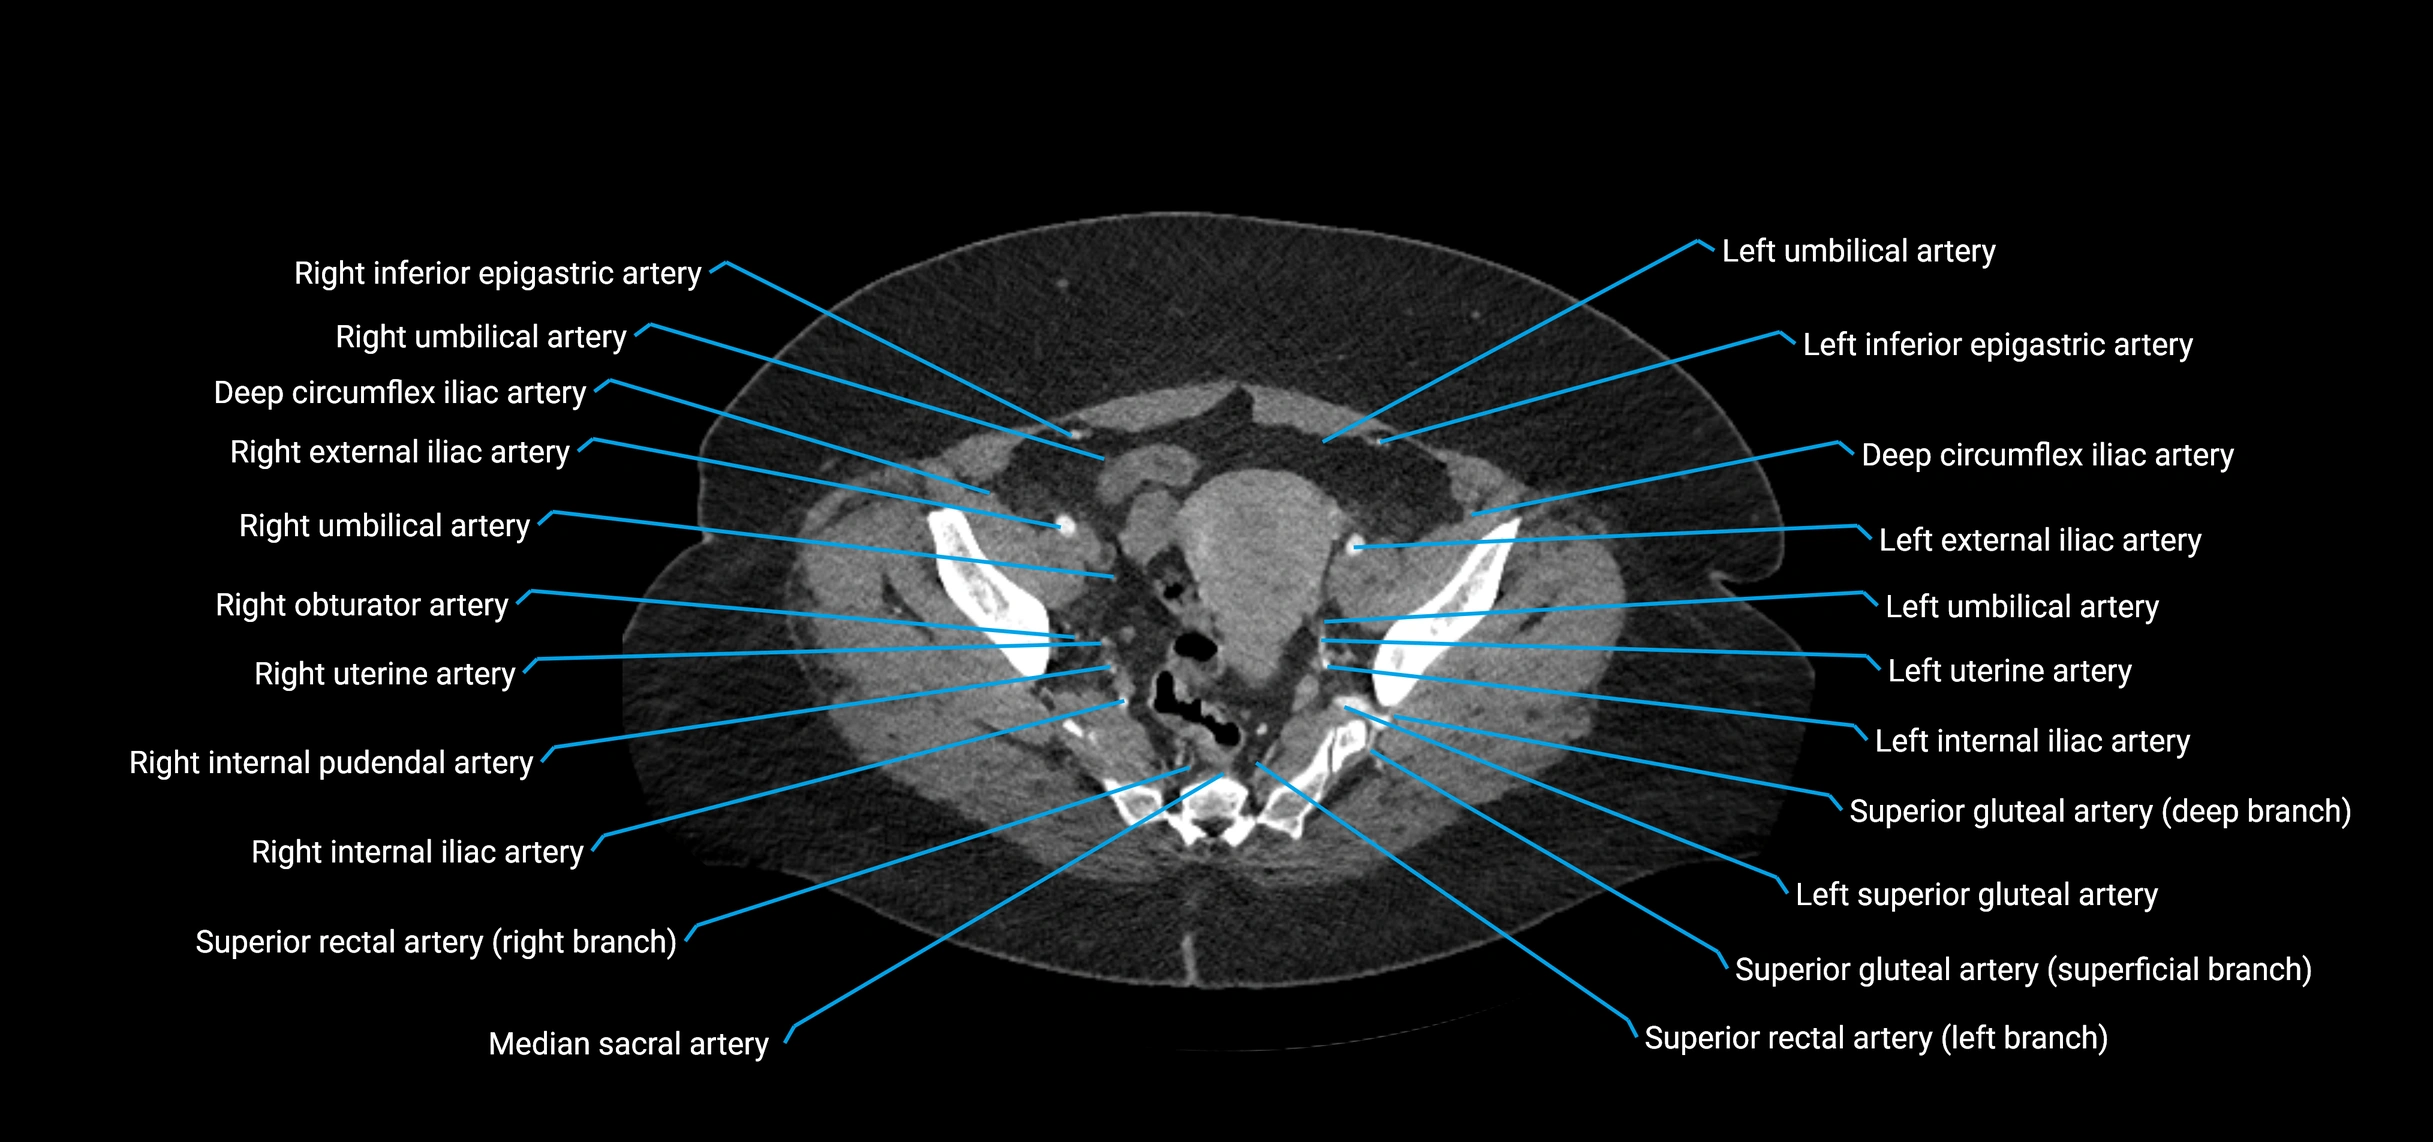

CT Appearance

Non-contrast CT:

• Appears as a tubular soft tissue structure anterior to vertebral bodies

• Calcified atherosclerotic plaques appear as hyperdense foci along the wall

• Useful for screening abdominal aortic aneurysm (AAA) size and mural calcification

Contrast-enhanced CT (CTA):

• Gold standard for abdominal aortic imaging

• Provides excellent detail of lumen, wall, aneurysm, thrombus, and branch vessels

• Multiplanar and 3D reconstructions help in aneurysm measurement, stent graft planning, and dissection evaluation

• Detects acute rupture, traumatic injury, or occlusion with high sensitivity

CT images

image